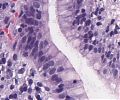

• Magenschleimhaut vom Antrum- und vom Corpustyp mit plasmazellreicher chronischer und granulozytär aktiver Entzündung

• Lymphofollikuläre Hyperplasie

• Nachweis unterschiedlich dichter, kommaförmiger Helicobacter pylori-Bakterien, die dem Oberflächenepithel aufsitzen